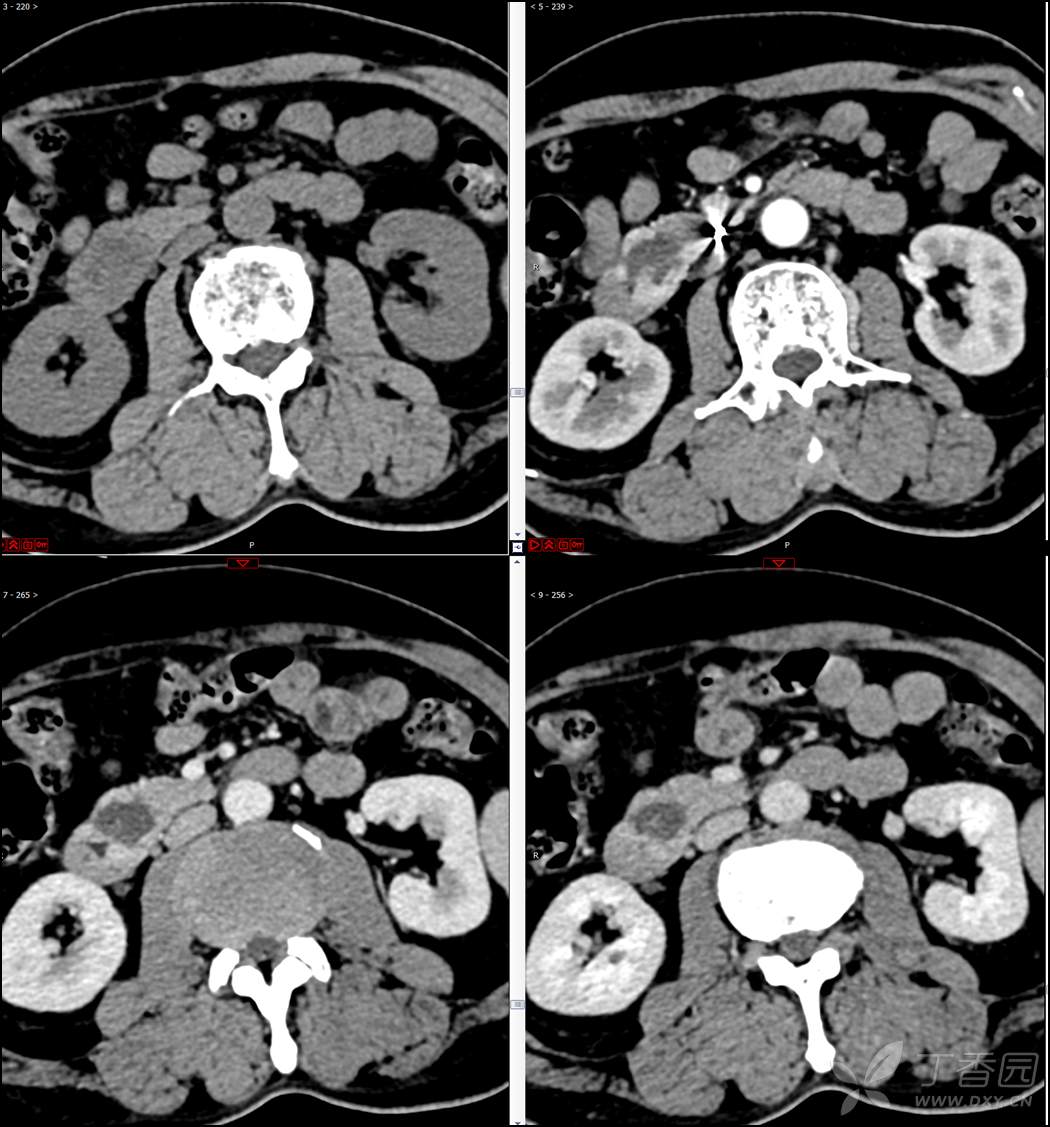

【影诊笔记521】老年男性,黑便就诊,请分析~『回帖即可查阅答案』

患者年龄:67岁

主诉:黑便1周。

现病史:患者1周前无明显诱因出现黑便伴头晕、心慌,无胸闷、胸痛,后仍间断黑便,2022-10-27就诊于某市中医院,行胃镜检查示:十二指肠溃疡伴出血,给予止血、抑酸等对症治疗,效果欠佳。今为行进一步治疗就诊于我院急诊,门诊完善新型冠状病毒核酸检测后以“十二指肠溃疡伴出血”收入我科。患者自发病以来,神志清,精神可,未进食,睡眠可,小便未见异常,黑便,近期体重无明显增减。